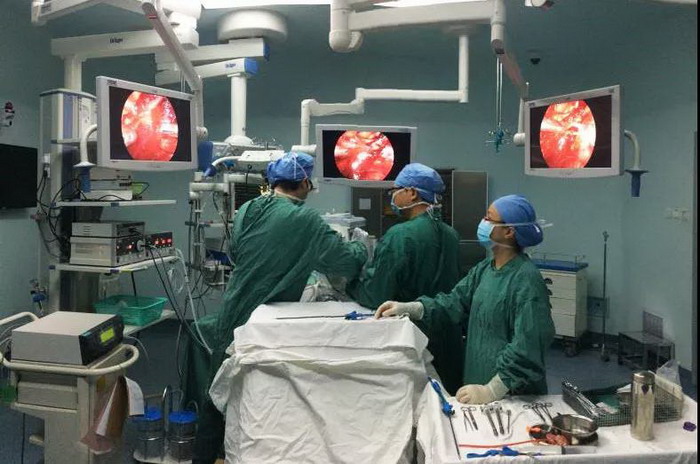

▲医生手术中

团队技术过硬为患者排忧解难

周主任及团队凭借过硬的技术,手术花了一个半小时便顺利完成,术后第2天何先生已能下床活动,术后5天康复出院,术后1月复查提示右肾功能几乎毫发无损,何先生的亲人和朋友都替他高兴,术后恢复的如此之快真是太神奇了。

我院外三科(泌尿外科)副主任医师唐炎权介绍说,在腹腔镜微创技术下进行右肾肿瘤切除术是泌尿外科最高难度的术式之一。

常规情况下,手术在分离出肾动脉后需要阻断肾脏血流再进行肿瘤切除,切除肿瘤并缝合切口后再恢复肾脏血供,由于肾脏血流受到阻断,肾脏功能会受到一定的损害;本科室引进的无血流阻断腹腔镜肾肿瘤切除术属国内最新技术,其无需阻断肾脏的血流,术后除切除的肾脏组织功能受到损害外,其它位置的肾功能不会受到损害,因此肾功能的损失更加少,对于肾功能的保护更有优势。